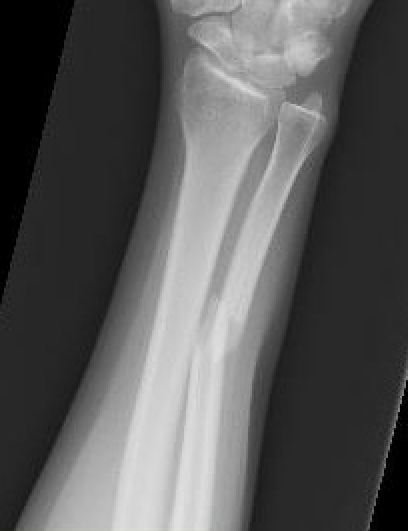

Distal 1/3

| Distal 1/3 | Middle 1/3 | Proximal 1/3 |

|---|---|---|

| Higher nonunion rates | Beware Monteggia / radial head dislocation | |